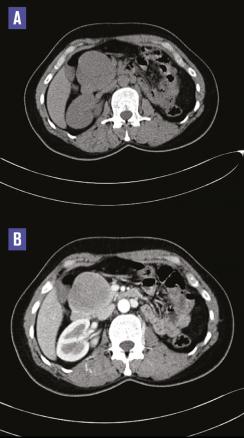

Cette femme de 38 ans était admise aux urgences pour des épigastralgies sans antécédent pathologique notable, avec une fièvre à 38,6 °C ; le bilan biologique mettait en évidence un syndrome inflammatoire sans perturbation du bilan hépatique. La tomodensitométrie abdomino-pelvienne sans et avec contraste réalisée (fig. 1 ) montrait une masse de la tête du pancréas, bien limitée, de 65 x 60 mm, isodense, réhaussée de façon hétérogène, délimitant des zones hypodenses. L’imagerie par résonance magnétique (IRM) pancréatique objectivait une masse de la tête du pancréas en isosignal T1, signal intermédiaire T2, de rehaussement périphérique délimitant une zone centrale liquidienne (fig. 2 ). Une duodéno-pancréatectomie céphalique était réalisée, permettant le diagnostic histologique de tumeur pseudopapillaire et solide du pancréas.